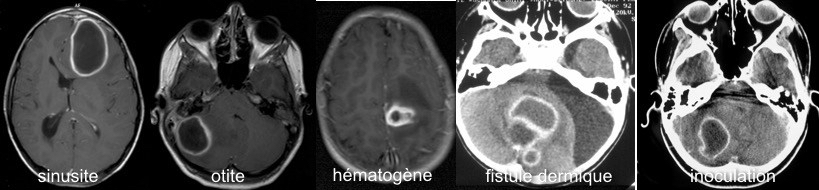

on distingue plusieurs entités cliniques

- les abcès d’origine ORL : sinusite ou otite, les plus commun, parfois favorisés par un traitement anti-inflammatoire intempestif.

- les abcès de cause locale : fistule dermique, inoculation traumatique

- les abcès d’origine hématogène : ils surviennent dans un contexte connu de cardiopathie cyanogène (devenue un cause rare d’abcès en raison des progrès de la chirurgie cardiaque), une fistule artérioveineuse pulmonaire (syndrome de Rendu-Osler) ou une infection bronchique chronique comme dans le syndrome de Kartagener.

le scanner n’est pas suffisant mais il peut montrer des signes d’ostéite en regard d’une sinusite. Le T1 injecté montre une prise de contraste en anneau mais peut faire errer vers un diagnostic de tumeur ; la séquence de diffusion montre un aspect très évocateur avec restriction de la diffusion.